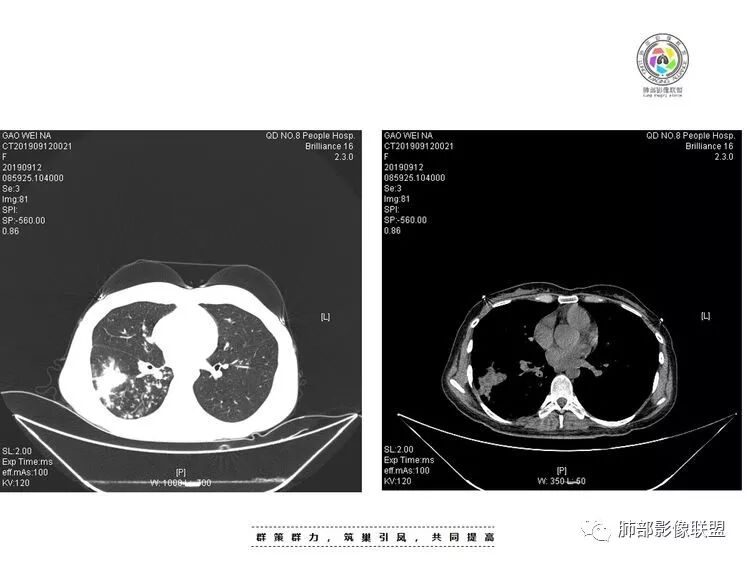

年轻女性,咳嗽咳痰(白黏痰)一月,加重一周,发热3天伴咯血。实验室:中性粒、CRP、血沉增高CT:右肺下叶不规则厚壁空洞伴散在树芽、小叶中心结节。空洞内壁光滑,似见液平。无胸腔积液及明显纵膈肿大淋巴结。给予左氧及美洛治疗12天复查CT,病灶明显吸收缩小。考虑感染没有问题。问题是单纯细菌感染还是结核感染?甚至二元?患者病史较长,临床与影像都有符合结核的表现,且左氧对结核治疗有效。因此,建议痰找抗酸杆菌,痰培养,并继续复查肺部CT。

患者青年女性咳嗽、咳痰1月,加重1周,发热3天。患者1月前受凉后出现咳嗽,咳少量白色痰,1周前咳嗽加重,痰量增多,为黄白色黏痰,偶有痰中带血,轻微胸闷,近3天来出现发热,最高体温38.4℃,伴乏力,食欲下降。辅助检查:血常规白细胞及中性分类 血沉 CRP均增高。胸CT:右肺下叶前基底段实变病灶内可见空洞,洞内可见气液平面,病灶周围及右肺下叶背段可见树芽征 、结节。经抗感染治疗,基底段病灶较前缩小,背段病灶 融合 增大。考虑良性病变,空洞性肺结核合并细菌感染。

女,28,咳嗽咳痰(白黏痰)一月,加重一周,发热3天伴咯血。实验室:WBC,中性粒、CRP、血沉增高CT:右肺下叶背段不规则厚壁空洞伴液平,内壁光滑,临近胸膜牵拉、糊墙,近端引流支气管壁厚,周围肺野散在树芽、小叶中心结节、斑片伴肺气肿,纵隔及右肺门有淋巴结,治疗后病灶缩小;考虑结核伴感染。

29岁女性,既往体健。咳嗽咳痰(白黏痰)一月,加重一周(黄白痰),发热3天伴咯血。血常规:中性粒、CRP升高,血沉增高。CT:右肺下叶不规则厚壁空洞伴散在树芽、小叶中心结节。空洞内壁光滑,似见液平。无胸腔积液及明显纵膈肿大淋巴结。予左氧及美洛西林舒巴坦治疗12天,临床症状减轻。复查CT见空洞明显吸收缩小,增强见薄壁空洞,内有液平,引流支气管增厚。考虑感染;是单纯细菌感染还是结核感染?还是细菌合并结核?建议痰找抗酸杆菌,痰培养,并继续复查肺部CT,可完善支气管镜检查。

2.右肺下叶片状影、结节影、硬树丫。单发空洞伴液平,内壁规则,外壁较清楚。相关支气管壁增厚。

影像符合典型继发性肺结核,或者说结核它是之前已经存在的。